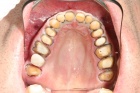

Leicht und praxisorientierte Fortbildung, um fit für das erste eigene Implantat zu werden. Halten Sie den Anschluss und bleiben konkurrenzfähig mit Ihren Kollegen.

Lernen Sie mit eindrucksvollen Full Hd Videos das operative Vorgehen wie bei einer Live OP, ohne die üblichen Wartezeiten.

Gewinnen Sie Einblicke, die Ihnen sonst verwehrt bleiben. Bekommen Sie Hintergrund Wissen, das es Ihnen möglich macht, die Qualitätskriterien Ihres Implantat Systems wirklich zu beurteilen.

Erfahren Sie, welche Fehler Sie unbewusst beim Implantieren machen können. Lernen Sie Ihr eigenes Implantat System anhand des Bohrprotokolls einschätzen und zu beurteilen. Wichtige knochenbiologische Kenntnisse.

Eignen Sie sich wissenschaftlich aktuelles Wissen an und vermeiden Misserfolge, die sich bisher nicht erklären konnten. Warum verkürzt eine perfekte Primärstabilität die Einheilzeit.